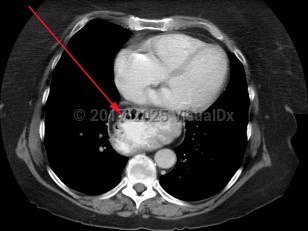

Hiatal hernias are classified as sliding or paraesophageal:

- Type I: sliding hernia – Most common type, due to progressive weakening of the gastroesophageal junction allowing a portion of the gastric cardia to slide upward with increased abdominal pressure, swallowing, and respiration. Patients with type I hernias are more likely to have gastroesophageal reflux disease (GERD).

- Types II, III, IV: paraesophageal hernia – Herniation includes viscera other than the gastric cardia, including gastric fundus and the colon. In type II and III hernias, the stomach becomes "inverted," possibly leading to gastric volvulus.